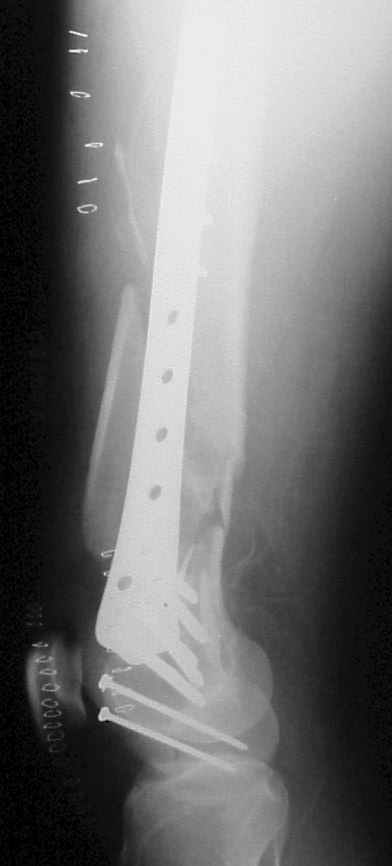

On Thersday afternoon he was alright, he is a very active man and he was moving well both knees. Later that evening he told me that while he was a little bit asleep he turned on the bed and felt pain and that the femur was loose. Here are the X-rays we took.

We are planning to reoperate him on Monday. Removing the screws from the LISS plate and drilling the medial cortex, using locking screws without the drilling tip.

In this case, the fixation might have failed because of inadequate purchase of the side plate to the shaft. I say this because the initial lateral xray shows that the plate seems to be fairly anterior to the mid-axis of the femoral shaft. Once the plate pulled off of the shaft, it continued to pull out of the distal segment. With the short unicortical screws used for shaft fixation, it is imperative that the plate be applied precisely at the midline (widest diameter) of the femur. If it is applied even slightly anterior or posterior to the midline, the screws just don¹t engage the cortex. You can¹t tell by feel, since the screws lock firmly into the plate.

The only guidance that imaging provides is to visualize the plate centered exactly on the bone on a good lateral projection, which is difficult to obtain intra-operatively. I have resorted to making a 3-4 cm incision at the top of the plate so that I can verify that the plate is exactly centered over the femur at its proximal tip.

A second "pearl" is to place at least one or 2 lag screws between the condyles for intrafragmentary fixation before applying the LISS. Although screws were used across the coronal plane (Hoffa) fracture, I do not see any lag screws from lateral to medial. The LISS screws are designed to maintain the reduction of the distal femoral condylar mass to the shaft, but they do not function as lag screws. The intra-articular portion of the fracture demands open reduction and rigid internal fixation according to established

principles; the LISS is used to then stabilize the reconstructed distal femur to the shaft.